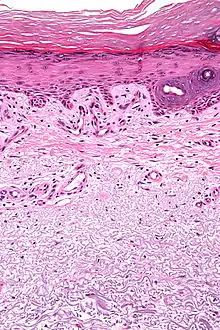

| Micrograph showing solar elastosis - grey, jumbled spaghetti-like material on bottom of image. H&E stain. | |

In the earlier stages of actinic elastosis, elastic fiber proliferation can be seen in the dermis. As the condition becomes more established, the collagen fibers of the papillary dermis and reticular dermis become increasingly replaced by thickened and curled fibers that form tangled masses and appear basophilic under routine haematoxylin and eosin staining. These fibers stain black with the Verhoeff stain.[2]